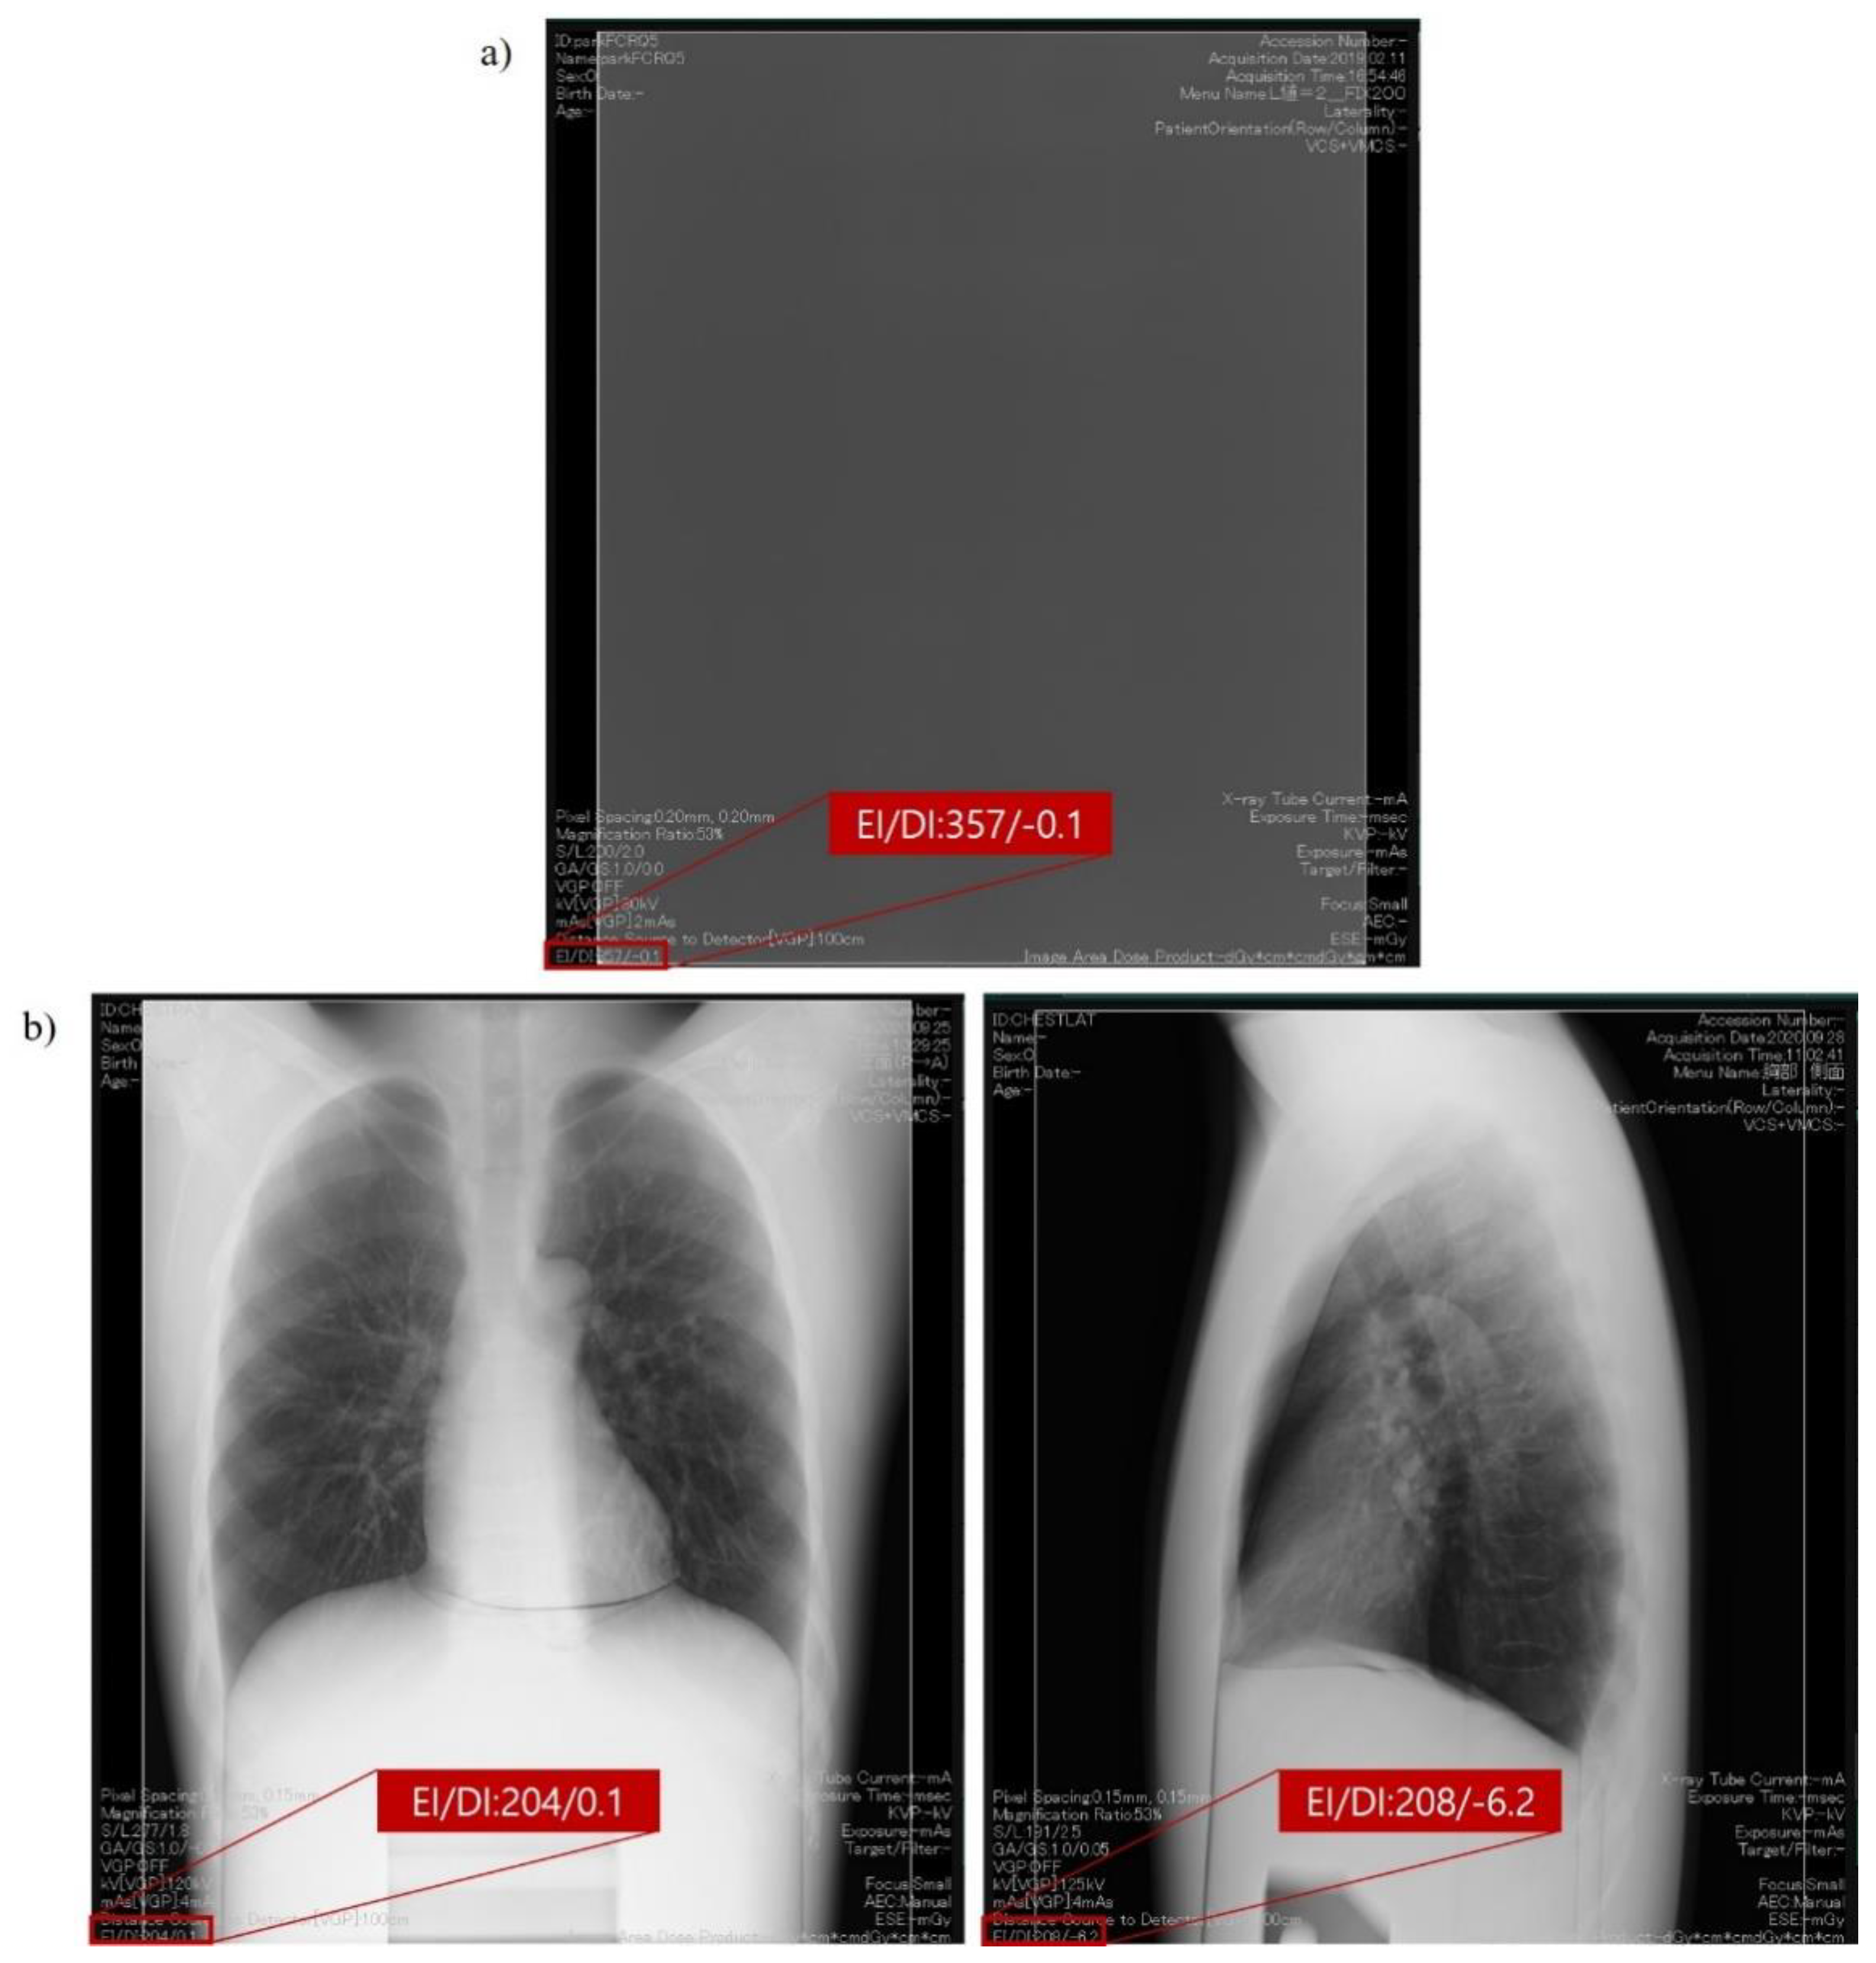

2.2. Exposure Index as per the International Electrotechnical Commission Standard Framework for Quality Assurance and Control of Digital Radiography Systems Used in This Study